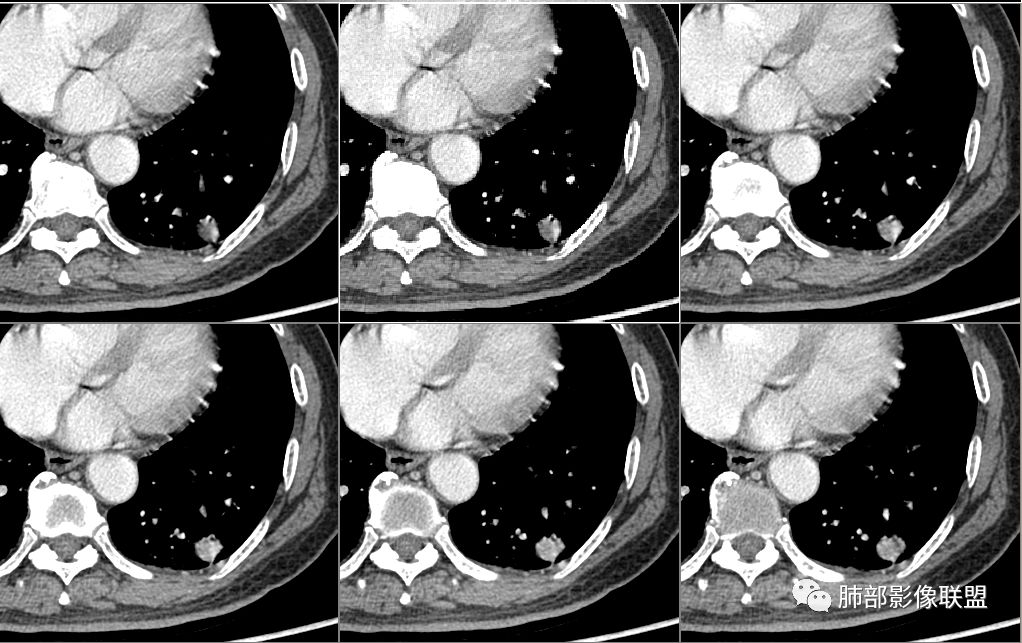

病例2资料

群内讨论

徐天鹏,宁夏海原县人民医院,放射:第二例结节局部膨隆,有血管进入,细支气管截断,考虑腺癌?

明日の路过:第二例,患者病灶在左肺上叶,分叶、空泡、血管供养征,感觉跟书上的恶性肿瘤图片一模一样。考虑恶性肿瘤可能。建议全身筛查后直接切除。

大雄:晨读第二个良性(坏死空洞明显而结节较小,且边缘收缩平直,有增强会更好)

晨: 第二例,患者病灶在左肺上叶,有分叶、空泡、血管供养征,气管截断,考虑恶性肿瘤,腺癌可能。

紫气东来:病例二,结节内空泡,支气管截断,血管进入,考虑恶性。

王开金江津中心医院呼吸科:病例二,左上叶类圆形结节,分叶,毛刺,血管集束证,空泡,考虑腺癌,鉴别结核球。

张立:

第二例,病灶中心有空泡,支气管病变边缘截断,腺癌?软骨型错构瘤?

欣:第二例:界清结节,有分叶,支气管截断,空泡征,腺癌,IAC

高广飞:有分叶,毛刺,空泡,腺癌?

飞鹰行动:

晨读病例二,左肺上叶小结节病灶,有分叶,支气管受阻塞,中断,内可见小泡征,首先考虑恶性病变,腺/鳞癌可能。

波波:第二结节局部膨隆,分叶,空泡,细支气管截断,考虑腺癌。

一切∮随缘:

晨读二:左肺上叶结节,深分叶,支气管堵塞并挤压,内部可见偏心性空泡,考虑恶性,腺癌,早期鳞癌。

大宝儿.蕊:上叶实性结节,边界清,分叶,短毛刺,小泡征,血管集束征,腺癌首先考虑。

应当说两例患者影像学表现都具有比较明显恶性征象,中老年男性患者,均都没有呼吸系统临床症状。

病例2肉瘤样癌的病理意见有些出乎预料,也充分说明病变及影像表现的复杂性。病灶小结节支气管截断、空泡、分叶、短毛刺、血管集束征等似乎均符合肺癌的影像特性。肺鳞癌及肉瘤样癌往往范围较小就可以出现坏死,但如果结节太小则很少能够在影像上观察到坏死区或空洞,没有增强扫描图像更是如此。